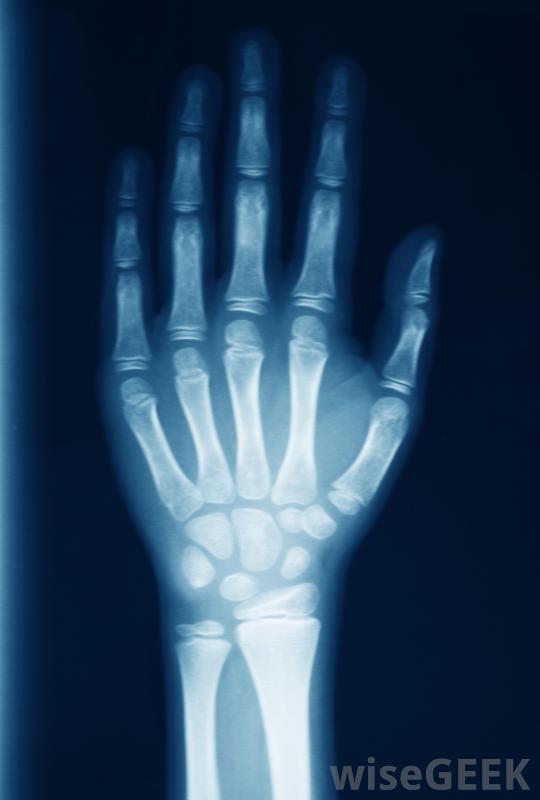

月骨是在腕关节上方的每只手中发现的一种骨头。它是一种位于手底部的腕骨类型。更具体地说,它位于每只手的外侧,在小指的下方,与拇指的底部相对。它位于舟骨旁边,与三棱骨、头状骨和钩状骨相邻最容易脱臼的腕骨。其功能与...

月骨的退化会导致严重的手腕疼痛。月骨呈新月形,因此得名。它有六个表面和韧带连接在周围相应的骨骼上。背部和手掌表面用于连接韧带。外侧,内、下表面与其他腕骨相互作用,外侧与舟骨、内侧与三角骨、下方与头状骨和钩状骨相互作用,内侧与三角骨相连,上表面与桡骨相连

月骨就在手腕上方。Kienbock病是一种主要影响月骨的疾病。这种疾病的主要症状是手腕和月骨周围的骨头疼痛。随着时间的推移,疼痛和其他症状都是由骨骼退化引起的,其整体原因尚不清楚,但被认为与骨供血不足或脱位有关。